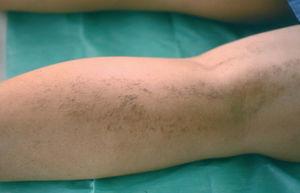

Una mujer de 21 años, sin antecedentes personales ni familiares de interés, consultó por presentar desde hacía 3 años unas pequeñas pápulas queratósicas, de coloración amarillenta-marrón-amarillenta, distribuidas linealmente a lo largo de la cara posterior de la pierna derecha. Las lesiones eran asintomáticas y no empeoraban con el sol ni con el sudor. No presentaba afectación de palmas o plantas, mucosa, ni anejos. Había recibido tratamiento con corticoides tópicos que empeoraban las lesiones (fig. 1).

Fig. 1.--Lesiones formando un patrón lineal.